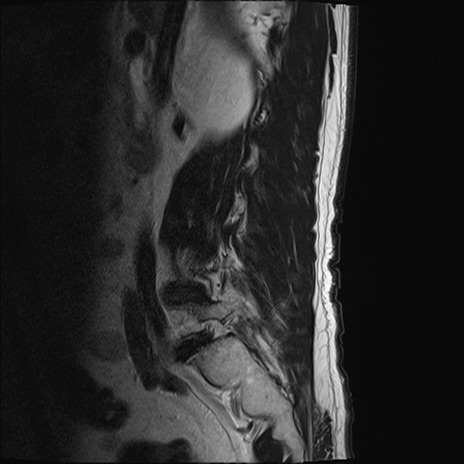

【整形】TIPS症例2 腰椎MRI T2WI(矢状断像)

【症例】70歳代男性

【主訴】左下肢痛

【現病歴】2週間前くらいから腰痛、左下肢痛あり。左臀部から大腿、下腿外側のしびれが常時ある。歩行とともに同部位の痛みあり。

【身体所見】Lasegue70-/60+、Bragard-/±、PTR ±/±、ATR -/-、IP 5/5、TA 5/4、TS 5/5、EHL 右第1足趾なし/3、FHL 5/5、hypersthesia(-)、足背動脈触知良好

異常所見と診断は?